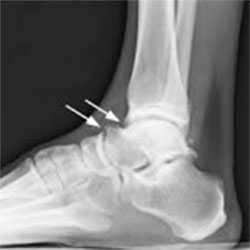

Рентгенограммы пациента с передним импиджмент синдромом

Выполняются рентгенограммы голеностопного сустава в двух проекциях. На обычных рентгенограммах остеофиты (костные шпоры) на голени или таранной кости чётко определяются. Можно выполнить боковые стресс-рентгенограммы, когда при приседании на корточки можно выявить соударение костных поверхностей в передней части голеностопного сустава, а при вставании на носки - соударение в задних структурах голеностопного сустава.

На рентгенограмме нередко можно увидеть гипертрофированный задний отросток таранной кости или os trigonum. В случаях перенесенных ранее травм мы ищем признаки несросшегося перелома в этой области.